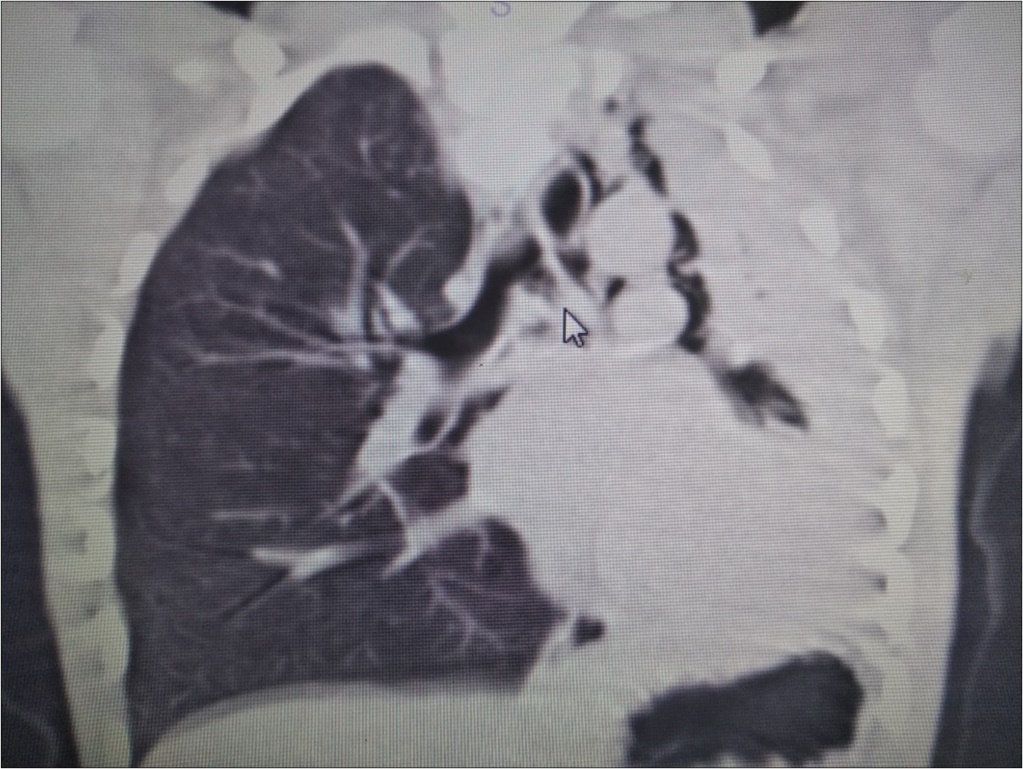

A 6 year-old boy was admitted to our hospital with the symptoms of upper respiratory tract infection (URI). He had hemoptysis 2 days prior to admission to hospital. On admission he had respiratory distress, fever (39°). Plain chest graphy demonstrated a complete opacification of the left lung (Figure 1). Thorax ultrasonography was normal and high resolution computed tomography (HRCT) of the chest revealed a 50-60% narrowing of the left main stem bronchus starting from carina downwards (Figure 2). Although there was no history of foreign object aspiration an emergent bronchoscopy was performed for a possible unnoticed aspirated foreign body. A bronchial cast located at the carineal bifurcation of trachea measuring 3x1 cm was detected and easily removed with forceps during bronchoscopy (Figure 3). The material was whitish, rubbery in consistency. Histopathologic examination of the cast revealed that it consisted of condensed fibrin, neutrophils and eosinophils. Culture was also obtained from the specimen for a possible bacterial growth. Following bronchoscopy the patient required mechanical ventilation for ventilatory support in the mode of high frequency oscillatory ventilation (HFOV) with supplementery oxygen in intensive care unit (ICU). In his 3rd hospital day, control chest graphy of the child showed complete opacification of the left lung and for a chance of residual cast in the tracheobroncial tree a repeat bronchoscopy was performed. Two seperate casts from the left main stem bronchus measuring 1.5x1 cm and 2x1 cm in length were removed with forceps and lavage with aspiration of both right and left main stem bronchus was performed. Following second bronchoscopy the transcutaneous oxygen saturation increased from 77 to 99 and control chest roentgenogram showed equal expension of both lungs. While in his stay in ICU, in addition to mediacal treatment, respiratory physiotherapy was performed regularly. He was medically treated with aerosolized dexamethasone with adrenalin. Bacterial test obtained from cast was found positive for Streptococcus viridans and vancomycin was started. On his 5th day in ICU, his respiratory status worsened and a chest graphy showed a decrease in expension of the left lung and a control bronchoscopy was performed. In this third bronchoscopy trachea and both right and left main stem bronchus were found to be patent but were found to have excessive viscous secretions. Pulmonary toilet including lavage and aspiration of thick tenacious secretions was performed. On day 12 he was transferred from the ICU and 1 week later he was weaned off the ventilator. He underwent pulmonary rehabilitation. During his 3rd year of follow up he has no further episodes of respiratory distress and he is disease free.

Figure 2.HRCT of the patient showing narrowing of the left main stem bronchus starting from carina downwards.

HRCT of the patient showing narrowing of the left main stem bronchus starting from carina downwards.

Radiographic findings are nonspecific and include atelectasis secondary to airway obstruction, hyperinflation due to air trapping, unilateral opacification, as seen in our case, bronchiectasis and lung infiltrates. It has been reported that HRCT may allow in some cases the visualization of bronchial casts in the airways of larger caliber 19. However the gold standard in diagnosing PB is bronchoscopy which reveals the airway obstruction by BC 3.